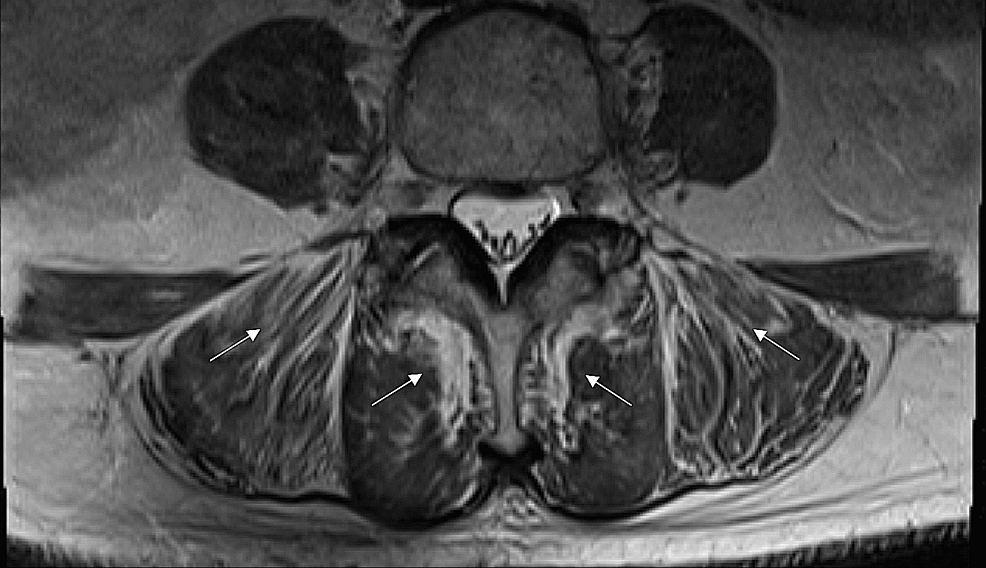

High-Intensity Statin With Severe Consequences: A Case of Non-autoimmune Rosuvastatin-Induced Myonecrosis

Statins constitute a cornerstone in the primary and secondary prevention of atherosclerotic cardiovascular disease (ASCVD). The routine use of these lipid-lowering agents may lead to unintentional neglect of their well-known...

Conclusions/Relevance: Ultimately, statin-induced myopathy may significantly hinder activities of daily living and impair quality of life. It is, however, a reversible condition if diagnosed and appropriately managed early on. Clinicians are encouraged to acquaint themselves with the symptomatology and relevant laboratory values that commonly...